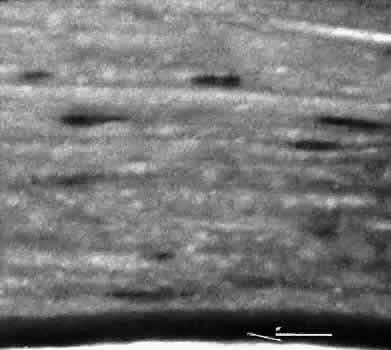

that results in reestablishment of functional ocular anatomy.1–3 The goal of therapeutic intervention in the setting of ocular trauma is to promote the repair process and to allow it to proceed as rapidly as possible and heal as completely as possible without compromising ocular function.4 CELLULAR AND EXTRACELLULAR COMPONENTS The four basic cell types found in wound healing are fibroblasts, vascular endothelial cells, inflammatory cells, and epithelial cells. Specialized cell types that participate in ocular wound healing include corneal endothelial cells, retinal pigment epithelial cells, and Müller cells of the retina. Specific cell populations enter an area of injury under the influence of complex biochemical and biophysical processes involving proteins of the extracellular matrix and the coagulation system. Intracellular proteins, such as tubulin and actin, andmyosin filaments function in cell locomotion. Extracellular matrix proteins, such as fibronectin, laminin, and type IV collagen, orient and regulate cell migration and adhesion.5 Coagulation proteins, such as von Willebrand's factor and plasminogen, alsofunction in regulating the cellular events of healing. Vascular endothelial cells are stimulated to leave their resting state and digest basement membrane, proliferate, migrate, and eventually differentiate under the direction of multiple angiogenic growth factors.6 A wound usually is filled first by a fibrin coagulum. Neutrophils, lymphocytes, and histiocytes (macrophages) enter the wound through fibrin scaffolding to clear necrotic debris and confine toxic or foreign substances. Granulation tissue often is the first type of reparative tissue in wound healing (Fig. 1). Although its composition varies somewhat, small-caliber vascular channels in a delicate collagenous stroma infiltrated by acute and chronic inflammatory cells generally characterize it. This amorphous tissue serves as a template for more definitive repair. Metaplasia is the transformation of a cell from one adult cell phenotype to a second cell phenotype. In advanced wound healing, fibroblasts acquire intracytoplasmic characteristics of smooth muscle cells (myofibroblasts).7 The myofibroblasts are able to contract and bring wound edges together. Vascular endothelial cells proliferate and migrate into the wound from preexisting adjacent vessels. The new “vessel” migrates initially as a solid bulb of endothelial cells. This solid cord of cells will canalize and differentiate into mature arterioles, venules, and capillaries. Fibroblasts grow into the wound in a radial manner but will eventually reorient and secrete collagen along lines of established tissue tension. Epithelial cells are found covering surfaces of tissue. Two distinct types of epithelial cells cover the ocular surface: corneal epithelial cells and conjunctival epithelial cells. Cell replacement is accomplished by stem cells located at the limbus for the corneal epithelium8,9 and at the mucocutaneous junction and possibly throughout the conjunctiva for the conjunctival epithelium.10 Migration and proliferation of surrounding healthy epithelial cells heal surface discontinuity. Apoptosis is a biochemical process leading to programmed cell death. Cell death in apoptosis results from intracellular messages. In necrosis, cell death results from toxic external factors (e.g., hyperosmolality). Apoptosis allows for elimination of entire populations of cells without tissue damage or an inflammatory response.11 Elimination of certain cells is advantageous in embryology (e.g., when scaffolding structures are no longer necessary as with the primary vitreous). In certain neoplastic conditions, however, defects in apoptosis may lead to disadvantageous accumulation of cells. Apoptosis also seems to be highly influential in all types of inflammation, including wound healing. In wound healing, apoptosis may function to control the type and degree of tissue response.12 In the anterior cornea, keratocytes have been observed to undergo apoptosis in response to wounding of the cornea.13,14 Abnormalities of apoptosis may be responsible for such conditions as keloid formation in the skin15 and keratoconus in the cornea.16 Wound healing of highly specialized tissues of the eye has several unique features. CORNEAL HEALING The healing of the cornea is unique relative to other soft tissues, because it lacks blood vessels and because it is lined anteriorly and posteriorly by layers of epithelial-like cells. Epithelial cells of the corneacan produce essential wound healing factors normally produced by platelets.17 Architectural repair is accomplished at the level of the corneal stroma. Abrasions are injuries generally involving only the superficial layer (epithelium) of the cornea (Fig. 2). Abrasions are commonly caused by mechanical injuries or anoxia resulting from contact lens overwear. Some or all of the layers of the surface epithelium are lost, but Bowman's membrane remains intact. After a delay of approximately 1 hour, uninjured epithelial cells at the margin of the wound loosen their intercellular and basal attachments and migrate en masse toward the injured area.18 The shape of the wound margin and the biochemical characteristics of the exposed tissue influence the direction and extent of the migration.19 If the entire corneal epithelium is abraded, migrating epithelial cells derived from the limbal stem cells are able to cover the defect completely within 48 to 72 hours. The epithelium will be much thinner than normal until mitotic division reestablishes normal thickness. Re-formation of epithelial basement membrane may not be detectable for as long as 6 weeks after injury.20 Clinically, the healed wound is transparent. Small defects of Bowman's membrane (Fig. 3) do not heal by fibrous proliferation of the stroma. The defect is filled by proliferating epithelial cells (epithelial facet formation) that reestablish the surface continuity of the cornea. The facet may be seen clinically as a focal, well-demarcated, superficial corneal opacity. A corneal foreign body causes this lesion most often. Penetrating corneal injuries involving at least one third of the stroma (Fig. 4) are covered initially by proliferating surface epithelium that may extend for a considerable distance into the stroma. The extent of corneal epithelial migration is controlled at least in part by contact inhibition of migration once contact with healthy corneal endothelial cells is established.21 Bowman's membrane has elastic properties that tend to pull the anterior margins of the wound apart. Exposure of the relatively dehydrated corneal stroma to tears and blood will cause swelling of the corneal stroma. This swelling of the stroma tends to close the wound. As the stroma heals, new collagen is produced by keratocytes or transformed monocytes. Epithelial cells will regress toward the surface. The repair collagen is different from the native collagen in size and in orientation. The healed wound is densely opaque and obvious clinically, but it may be detected histologically only by the break in Bowman's membrane. Full-thickness wounds of the cornea are associated with retraction of Descemet's membrane and separation of the posterior aspect of the wound (Figs. 5 and 6). Secondary aqueous, a proteinaceous coagulum, may seal the wound posteriorly until healthy surrounding endothelial cells can spread and migrate into the injured area. Mitotic division of the endothelial cells possibly plays an important role in younger patients but probably is not clinically significant in adults. Ultimately, migrated endothelial cells will produce a new Descemet's membrane (Fig. 7).22–25 The portions of Descemet's membrane displaced into the stroma are not resorbed, but remain as the histologic marker of the site of injury. The anterior cellular surface repair of migration and mitosis of epithelial cells is the same as that described for more superficial corneal wounds. The important exception is that with full-thickness injuries, there is a risk of surface epithelial cells migrating along the posterior surface of the cornea or the anterior surface of the iris to the trabecular meshwork. The displaced epithelial cells will cause scarring of the trabecular meshwork and secondary open-angle glaucoma. CONJUNCTIVAL HEALING Conjunctival healing differs from corneal healing because of the presence of blood vessels and a lymphatic system. The conjunctival epithelium heals by migration and mitosis.26 Conjunctival stem cells are thought to originate at the mucocutaneous junction and migrate to the fornix.27 Goblet cells are produced by epithelial progenitors and appear once conjunctival epithelial cell continuity has been reestablished.28,29 The presence of vascular tissue in the substantial propria of the conjunctiva allows for the formation of granulation tissue and scar tissue, as found in soft tissues elsewhere. SCLERAL HEALING The sclera itself does not participate directly in wound healing. Partial-thickness injuries are healed by formation of granulation tissue from the epi-scleral tissue in external wounds or from uveal tissue in internal wounds (Fig. 8). Full-thickness defects of the sclera heal by granulation tissue originating in the episcleral tissue and uveal tract. Mitomycin is used in filtering procedures specifically to prevent the formation of granulation tissue and promote establishment of an aqueous fistula.30 SURGICAL LIMBUS HEALING Currently, there is a trend for the site of the cataract wound to shift from the limbus to the peripheral cornea31 to reduce induced astigmatism32 and to shorten the natural history of cataract wound healing.33 The healing of the wound is similar to that found in central corneal incisions. Healing at the site of a limbal surgical incision involves a combination of the features of repair of the cornea, conjunctiva, and sclera (see Fig. 5). Conjunctival epithelium will heal over an area of granulation tissue originating from the substantia propria of the conjunctiva and the episclera. The granulation tissue seals the wound if the wound edges are well apposed. The remainder of the healing process is similar to the healing of an external scleral wound. Granulation tissue is not formed in the internal portion of the wound because the uveal tract is not involved. The internal wound is healed by endothelial migration and reformation of Descemet's membrane in a manner outlined above for full-thickness corneal wounds.34,35 Because of the lack of blood vessels, the rate of wound healing is slow relative to that of the skin. Whereas an injury to the skin may have regained its tensile strength in 7 to 10 days, injuries to the surgical limbus may require as long as 12 months to regain a stable tensile strength. The tissues of the wound remain structurally weaker than the surrounding uninjured tissue (Fig. 9). The healing of a clear corneal cataract incision proceeds as described above. UVEAL HEALING Wound healing of the posterior uveal tract follows the general principles for healing of vascularized tissue. The iris, however, heals differently. When the iris wound is perpendicular to its circumferential ridges, such as in a typical peripheral iridectomy or iridotomy, the cut edges pull apart. Granulation tissue does not form to close iridectomy incisions probably because of the inhibitory effect of the aqueous flowing through the opening of these small incisions. Iridotomies created by argon laser (Fig. 10) may be anatomically closed by apparent migration of iris pigment epithelium.36,37 LENS HEALING Proliferation and fibrous metaplasia of the lens capsular epithelium (Fig. 11) may close small rents through the lens capsule. After maturation of the fibrous tissue, the most superficial epithelial cells will form a new lens capsule. Most wounds to the lens, small and large, result in cataracts. Small wounds, however, may result in tiny focal opacities.38–39 Lens epithelial cells undergo fibromyoblastictransformation when stimulated by injury. The transformed cells are able to produce type I and type III collagen and glycosaminoglycans.40 This is the fundamental process resulting in opacification of the posterior lens capsule after extracapsular cataract extraction or phacoemulsification.41 Apoptosis (programmed cell death) also plays a role in the formation of secondary cataracts.42 RETINAL HEALING Wound healing of the neurosensory retina follows the principles of wound healing. There is an initial removal of all necrotic tissue by phagocytosis followed by proliferation of cells to form a chorioretinal bond. The healing, however, is modified in most instances by the lack of participation by the blood vessels.43–45 Astrocytes from the neurosensory retinaproliferate from the peripheral viable tissue into the wound and downward into the area of the subretinal space (Fig. 12). Retinal pigment epithelial cells from the peripheral viable tissue undergo fibrous metaplasia and proliferate upward into the area of the subretinal space. When the two proliferating cell types unite, a tight chorioretinal bond is formed. Increased retinal adhesiveness has been estimated to be 140% of the normal degree of adhesiveness 2 weeks after photocoagulation.46 Retinal holes may heal spontaneously if supported by an intact vitreous base or if located adjacent to the retinal pigment epithelium (Fig. 13).47,48 For the retinal pigment epithelium to differentiate, it must be in contact with overlying retinal pigment epithelium.49 Choriocapillaris repair from a photocoagulation wound of the retina appears to proceed in a manner similar to that of repair of capillary thrombosis in other tissues.50 The vascular repair process may not reproduce the lobular architecture of the native choriocapillaris.51 The choriocapillaris may regenerate in areas of restored retinal pigment epithelium.52 Proliferative vitreoretinopathy is an expression of abnormal retinal wound healing.53 Interruption of Bruch's membrane may allow the ingrowth of fibrovascular tissue from the choroid into the subretinal space, resulting in a modified granulation wound healing process and subretinal scarring.54 |